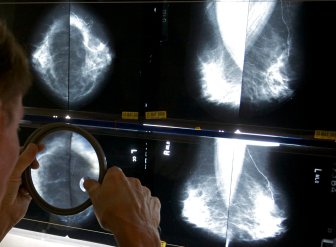

Pandemic worsened gaps in care, led to 30% fewer cancer diagnoses: Alberta doctor"The pandemic has made these gaps in cancer diagnosis worse and has resulted in a decrease by more than 30 per cent during the first wave."HealthDec 14, 2020